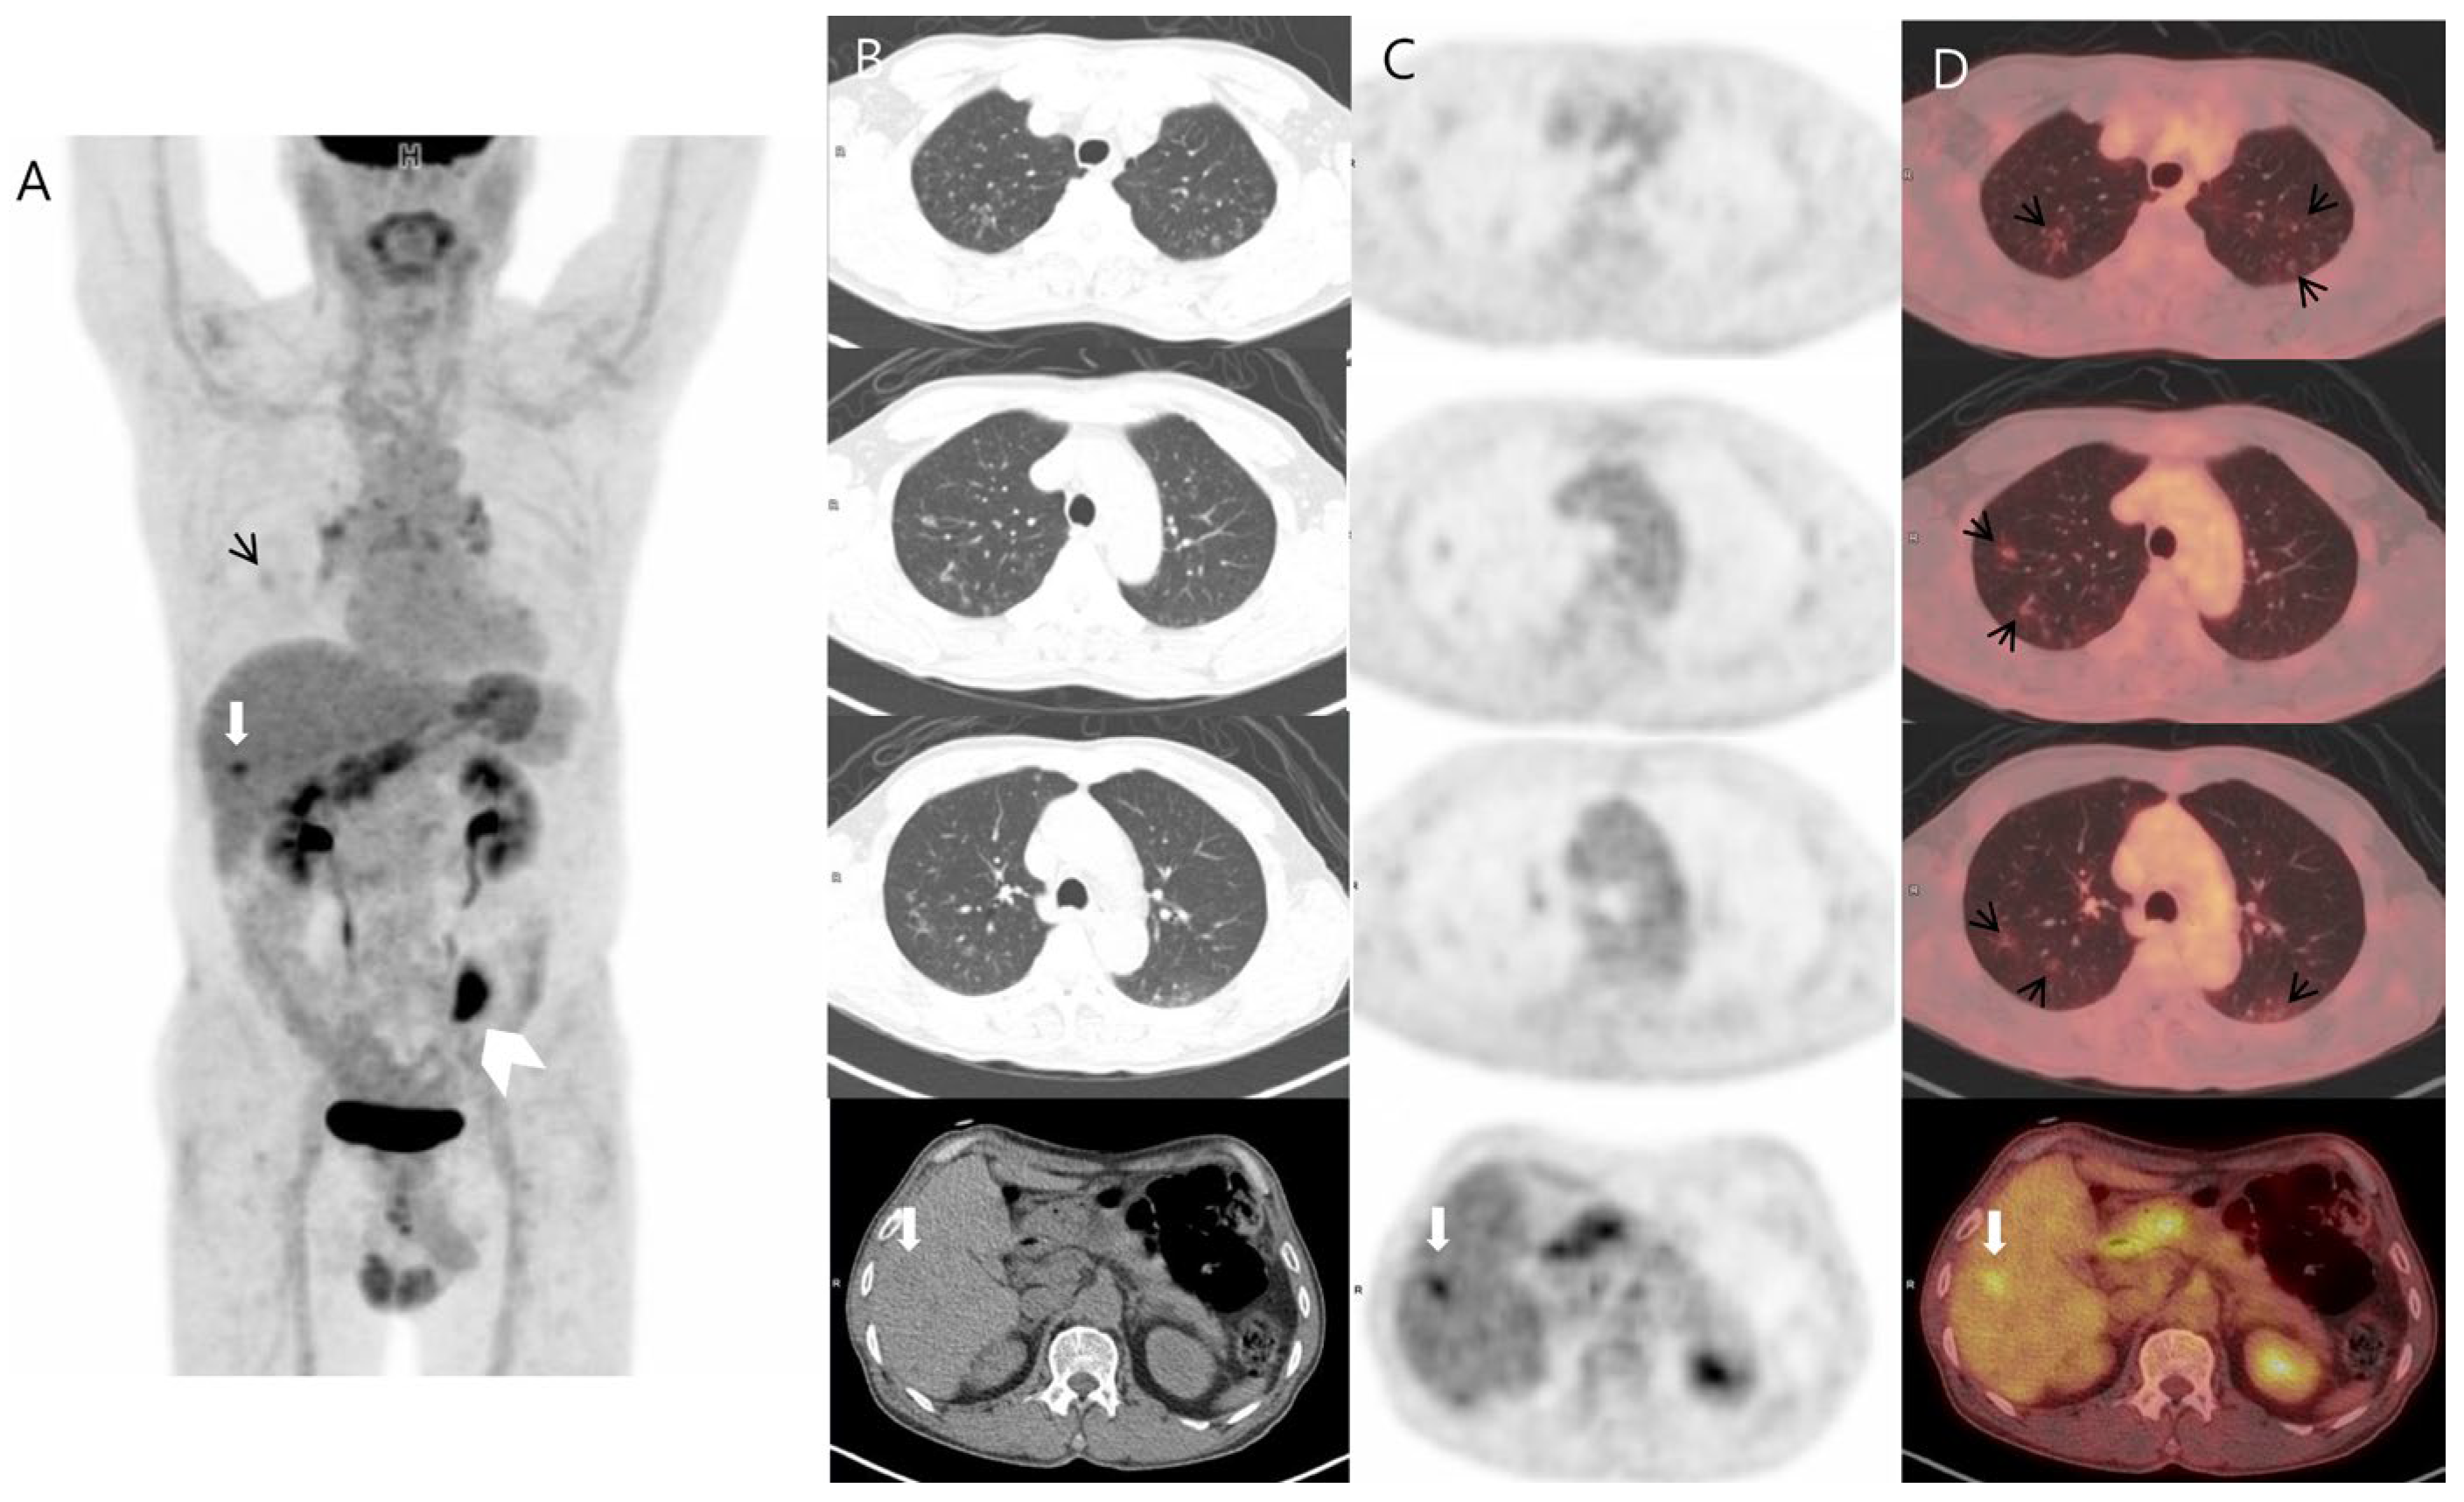

A 76-year-old man was diagnosed with colon cancer via a routine health examination, including a colonoscopy. As for colon cancer staging, chest computed tomography (CT), abdominal CT, and 18F-FDG positron emission tomography–CT (PET–CT) were performed. 18F-FDG PET–CT revealed a hypermetabolic mass in the sigmoid colon, representing colon cancer. It also demonstrated a mild hypermetabolic nodule in segment 5/6 of the liver and multiple mild hypermetabolic cavitary nodules in both lungs (Figure 1). Based on these findings, we suspected sigmoid carcinoma metastasized to the lung and liver as the first differential diagnosis.

Figure 1.

Three-dimensional maximum intensity projection (A) and transaxial images ((B) CT; (C) PET; (D) fusion) of 18F-FDG PET–CT demonstrated, in addition to a hypermetabolic mass in the sigmoid colon (white arrowhead), abnormal multiple cavitary pulmonary nodules with mildly increased FDG uptake (black short arrows) and a focal hypermetabolic nodule in the right hepatic lobe (white arrow). The maximum standard uptake values were 1.81 for the pulmonary nodule and 4.8 for the liver lesion.